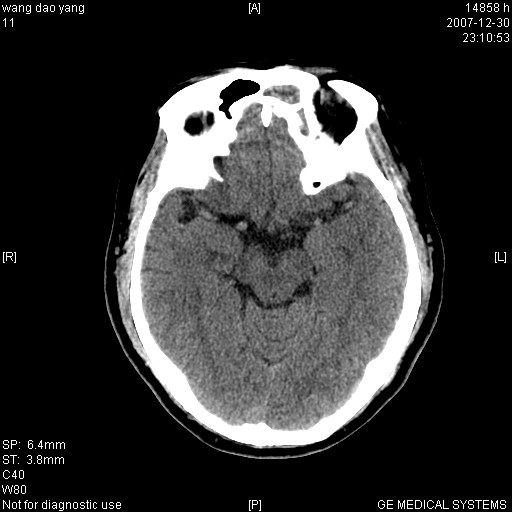

因外伤做ct

右枕部有没有硬膜下血肿?

1筛窦血肿2球后血肿

病灶形态不规则,临床有外伤史,支持考虑:球后血肿!!!

球后肌锥内小团块状软组织密度影(性质待定);建议:行ct增强扫描或mri检查。